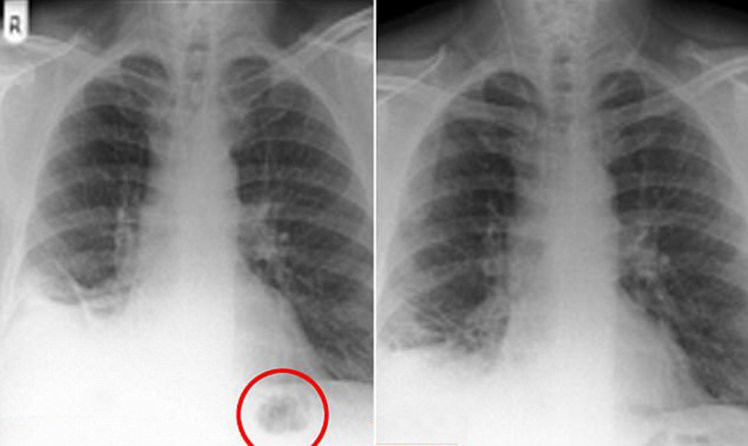

Öksürük şikayetlerinin sıklıkları arttıkça hastanede çekilen röntgen sonuçlarında, uzun süredir sigara içen hastanın ciğerinde bir tümör olduğundan şüphelendi.

YILLARCA HİÇBİR SORUN YAŞAMADI Tümörü çıkarmak için yapılan ameliyatta doktorlar tümör yerine oyuncak bir trafik konisi çıkardı. British Medical Journal'da yayınlanan araştırmada hastanın yıllarca hiçbir sağlık sorunu yaşamadığı, sadece son zamanlarda öksürmeye başladığı belirtildi.

BBC Türkçe'nin haberine göre, doktorlara göre bu cismi erken yaşta yutması nedeniyle gelişmekte olan ciğerleri buna uyum sağladı.